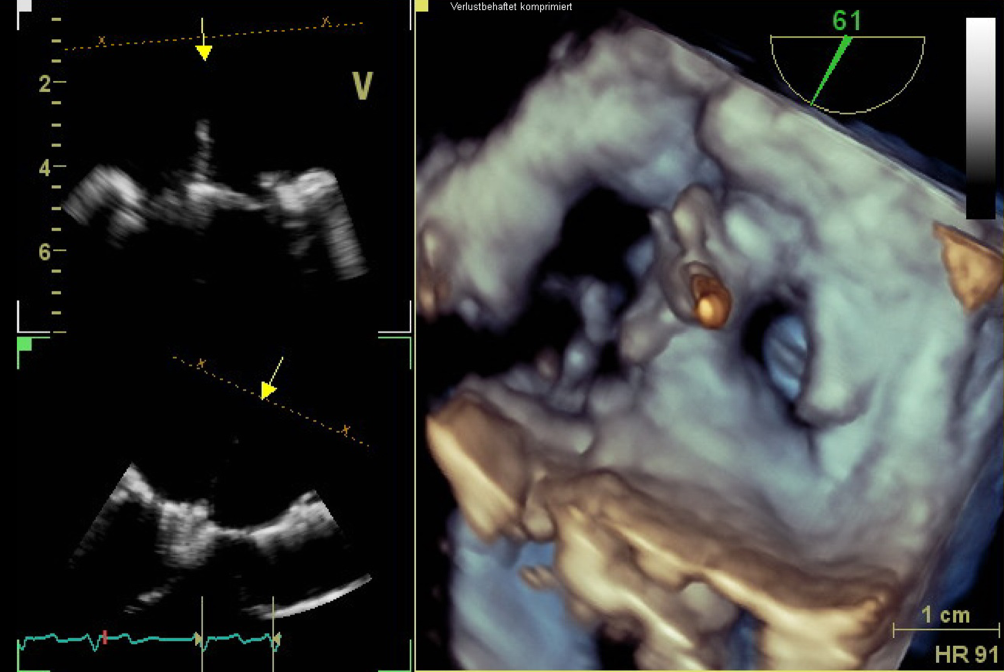

Abb. 3

Transösophageale Echokardiographie. 3‑D-Ansicht mit Aufsicht auf die Mitralklappe. Zu sehen ist das PASCAL-Device (Edwards Lifesciences) zwischen den Segmenten A2 und P2

Abb. 4

Transösophageale Echokardiographie. 2‑D-Ansicht im 4‑Kammer-Blick mit Farbdopplerdarstellung der Mitralklappeninsuffizienz nach PASCAL-Implantation (Edwards Lifesciences)